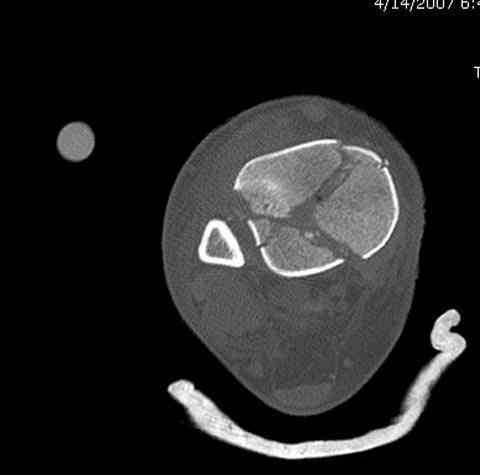

Добавлены КТ снимки. Прошу прощения за качество.

С уважением, Коваленко А.Н.

Good day colleague! Iam very happy that only one surgeon recomended immediately to do operation even without CT.X-ray, that you sended,is bad quality.According to CT this is very difficult case.My opinnion in the first distraction by external fixator,prefere Ilizarov,for arrival by ligamentotaxis reduction of gross displasement,rigid fixation of lateral malleolus.

After that under C-arm rentgen you can tray reduction of other fragments open or clouse method

Condition of soft tissue is very mportant.Are you patient has ischemic changes? So ten days sometimes isn't enough,and you can get problemms with cloused operation wounds.